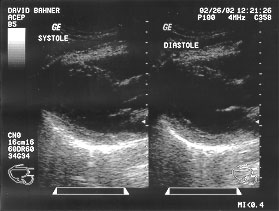

Cardiac cycle - long parasternal view